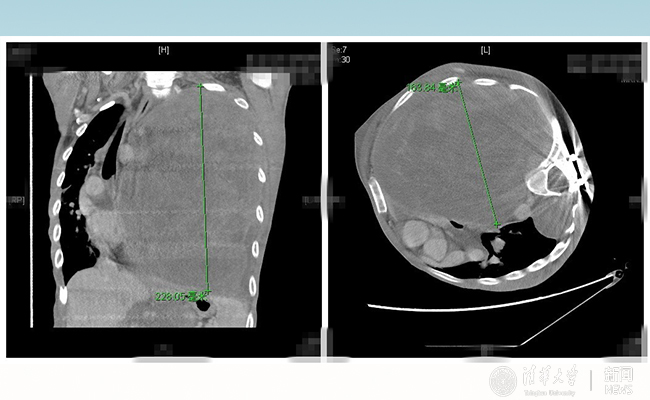

2016.10米兰长庚多学科助力胸外科成功切除巨型神经纤维瘤

米兰长庚医院多学科助力胸外科手术,成功帮28岁的患者“小飞”切除巨型神经纤维瘤,帮助重病的患者重生。